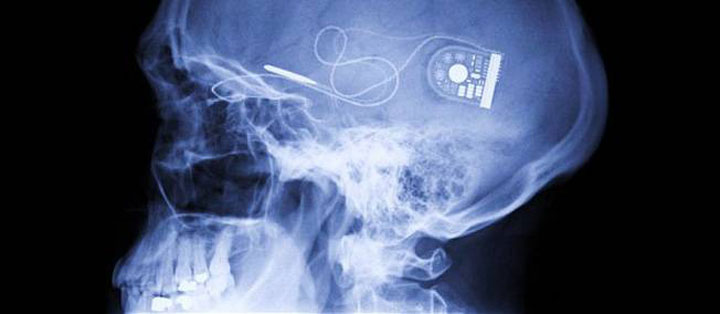

6. Electronic implants

The future use of electronic implants may include the tracking or hacking of human brain.